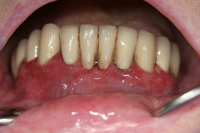

Akut inflammatorisk destruktiv sjukdom i gingiva och parodontium.

Karakteriseras av approximala nekrotiska och fibrintäckta sår (nedsmälta papiller) som är smärtsamma vid beröring och mycket lättblödande.

Patienten kan ha påverkat allmän tillstånd och ofta foeter ex ore.

I anamnesen förekommer ofta kombination av nedsatt immunförsvar, rökning, stress och dålig munhygien. HIV/Aids kan finnas som bakgrundsfaktor.